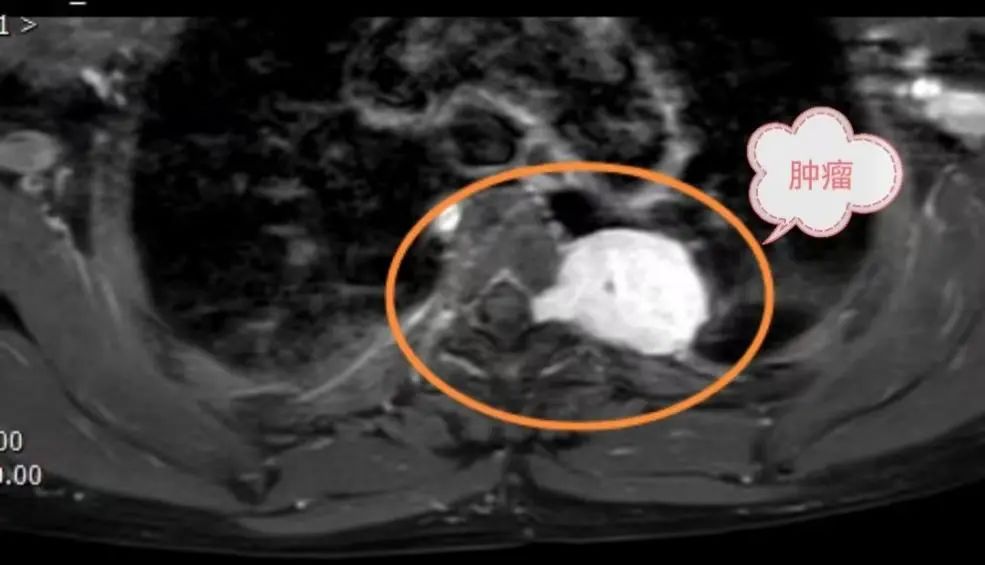

图为:术前磁共振提示后纵隔肿瘤经椎间孔侵入椎管

患者因后纵隔肿瘤经椎间孔长入椎管,病情少见且有很高的手术风险——椎间孔内肿瘤压迫脊髓神经可能致瘫,完整切除肿瘤才能最大限度去除病变并降低术后复发。然而由于肿瘤植根于椎间孔并向椎管内生长,稍有不慎就会造成难以控制的髓腔内出血,严重的会造成截瘫甚至危机生命,国内外此类情况均有报道。